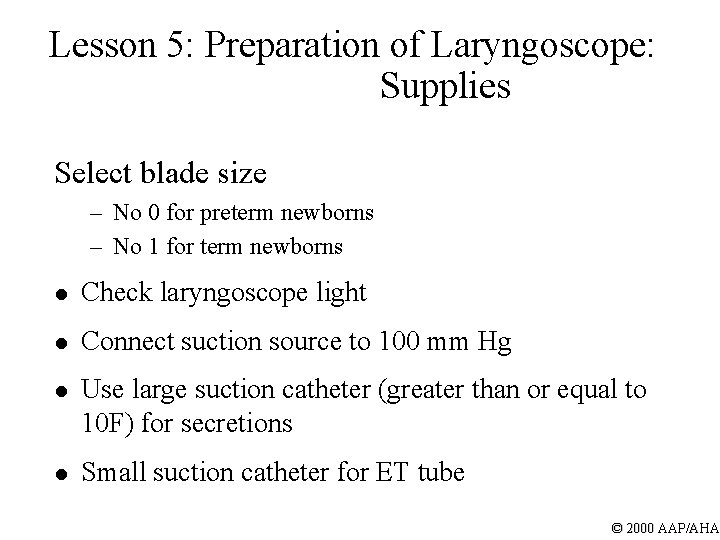

Lesson 5: Preparation of Laryngoscope: Supplies Select blade size – No 0 for preterm newborns – No 1 for term newborns l Check laryngoscope light l Connect suction source to 100 mm Hg l Use large suction catheter (greater than or equal to 10 F) for secretions l Small suction catheter for ET tube © 2000 AAP/AHA